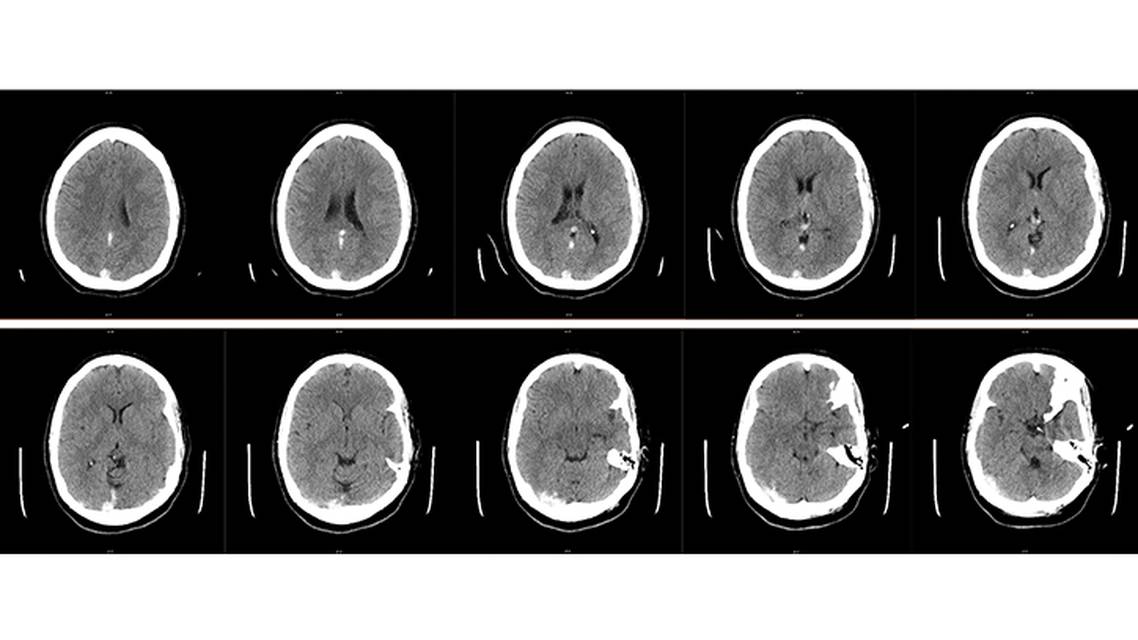

PW, aged late 20s , who had a history of migraines and current combined oral contraceptive use, presented to the emergency department (ED) with a severe headache. PW was treated for migraine and released from the ED. Over the next 2 days, PW experienced worsening headaches, and began having episodes of vomiting. Progressive clinical deterioration culminated with an episode of loss of consciousness, and PW returned to the ED 2 days later. On arrival, PW reported an inability to see or stand properly. While in the ED, PW had a generalized tonic-clonic seizure, was treated promptly with multiple antiepileptic drugs, and underwent intubation for airway protection. CT angiography showed a massive cerebral venous sinus thrombosis (CVST) of the right transverse, straight, and superior sagittal sinuses, complicated by diffuse cerebral edema (Figure 1). In addition, many features were concerning for elevated intracranial pressure (ICP), including severe headaches, vomiting, loss of consciousness, lack of response to noxious stimuli, and triple flexion of lower extremities. Given the severity of the presentation, PW was started on anticoagulation and transferred immediately to a tertiary center for neurosurgical intensive care.

Upon arrival, PW underwent emergeny cerebral angiography and venography to evaluate vessel morphology and flow patterns and to assess candidacy for intervention with thrombolysis or thrombectomy. Massive and extensive CVST was confirmed, with no contrast filling of the superior sagittal sinus, straight sinus, vein of Galen (VOG), torcula, or right transverse or sigmoid sinuses. Given the refractory clinical status and the radiologic presence of substantial CVST, both thrombolysis and thrombectomy were attempted. A total of 4 mg of tissue plasminogen activator (tPA) was injected into the superior sagittal sinus and a Solitaire X Revascularization Device (6 x 40 mm; Medtronic, Minneapolis, MN) and an EmboTrap II Revascularization Device (605 x 45 mm; Cerenovus, Irvine, CA) were used with a RED 72 aspiration catheter (Penumbra, Alameda, CA) to make multiple mechanical thrombectomy passes at the superior sagittal sinus. These interventions resulted in partial recanalization and improved bilateral cortical venous flow. An additional 4 mg of tPA was infused into the torcula and origin of the straight sinus; however, attempts to cannulate and catheterize the straight sinus were unsuccessful (Figure 2).